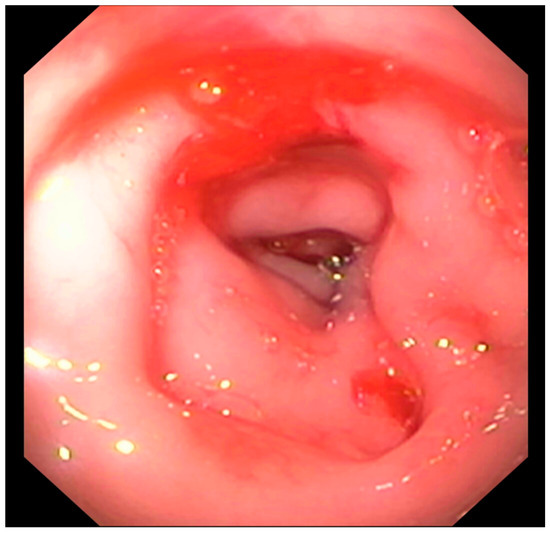

3.2.4. Endoscopic Findings